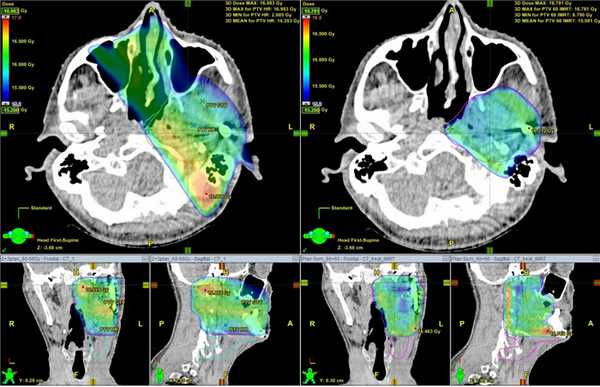

Ниже представлены данные снимков, демонстрирующие более точное распределение дозы в облучаемом объеме и снижение нагрузки на здоровые ткани (IMRT - справа).

Применение модулированной по интенсивности лучевой терапии (IMRT) возможно только при наличии современных линейных ускорителей, систем планирования лучевой терапии, средств для проведения подготовки к лучевому лечению (специализированный компьютерный томограф, фиксирующие устройства и приспособления, магнитно-резонансный томограф) и квалифицированного медицинского персонала. Все это позволяет сделать подход к каждому пациенту индивидуальным, ориентированным на безопасность и максимальный результат за минимальное время. В настоящий момент наша Клиника является единственным в Санкт-Петербурге и Ленинградской области медицинским учреждением, располагающим всем необходимым арсеналом для осуществления данной методики облучения.